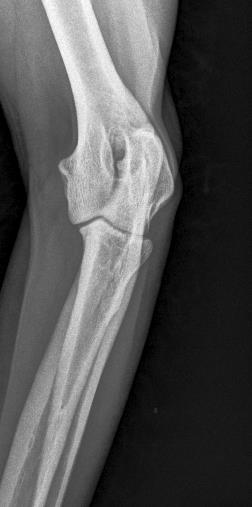

• ED Abklärungen

• Frakturbeurteilung